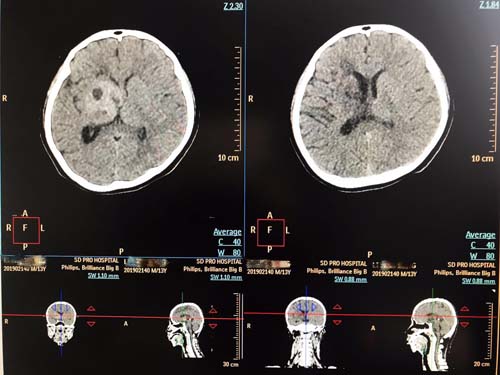

肿瘤治疗中心CT模拟控制室的电脑前,一位神情焦虑的父亲紧紧盯着屏幕上儿子的脑部CT影像,当主任医师告诉他,孩子的CT影像显示病理阴影已基本消失,恶性肿瘤的生长已经得到有效控制时,这位父亲激动的热泪盈眶并向在场的医务人员表示感谢,这一幕触动了在场所有人的心弦,大家由衷的为他和孩子感到高兴。

像这样成功的病例并非个例,山东省立医院肿瘤治疗中心依托自身雄厚的医资力量,发挥先进医疗资源优势,运用国际国内前沿诊疗方法,结合具体病情,量体裁衣,为每名患者制定个体化治疗方案。科室拥有国际先进的飞利浦16排大孔径CT模拟定位机PHILIPS Brilliance Big Bore CT和GE/美国Discovery RT临床版全视野诊断级大孔径 CT,是目前国际最先进的大孔径CT模拟机。先进的4D-CT定位功能,配合个体化治疗计划,实现真正、完整的4D-CT模拟,能够快捷的为肿瘤放疗患者进行精准的定位,同时也减少了由于患者呼吸、心跳带来的剂量误差,在增加肿瘤治疗疗效的同时,降低正常组织的不良反应,让放疗摆位更准确,剂量误差更小,使放疗技术水平又上了一个新的台阶。